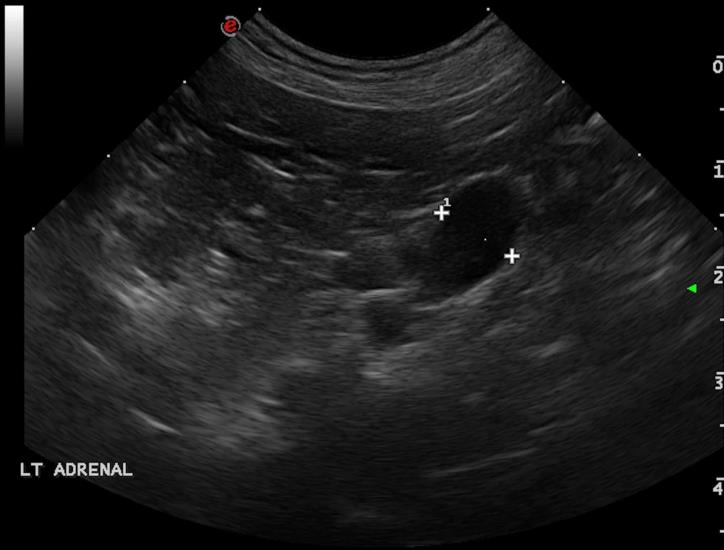

A 8-year-old cocker spaniel was referred for polyuria/polydipsia and polyphagia. The abdominal ultrasound revealed bilateral symmetric adrenal enlargement (images below). A CT scan of the head was performed. A round, 7mm, contrast-enhancing nodule was found at the level of the pavement of the sella turcica, in the hypophyseal fossa (green arrowheads).